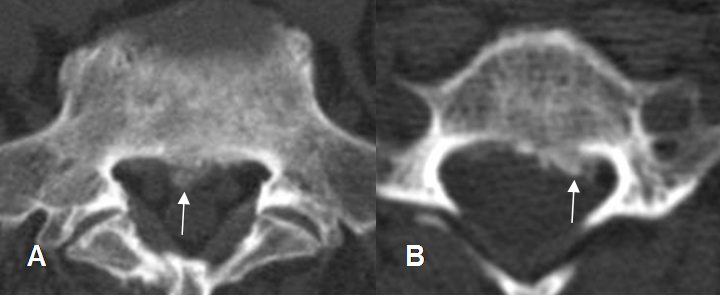

Fig 52. Canal estrecho central.

A: TAC axial lumbar y B: TAC axial cervical. Osteofito central (Flecha delgada) y paramediano izquierdo (Flecha gruesa), que obliteran la grasa peridural.